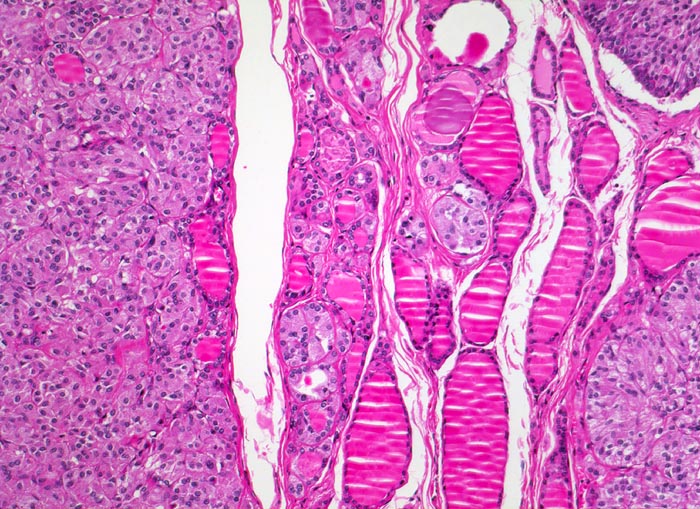

• Mehrere, unscharf begrenzte, unbekapselte Tumorknoten mit desmoplastischem Stroma in ansonsten unauffälligem Schilddrüsenparenchym.

• Die Tumorinfiltrate bestehen aus soliden und kribriformen Verbänden spindeliger Tumorzellen.

• Mehrere Herde hyperplastischer C-Zellen im nicht-neoplastischen Schilddrüsenparenchym als möglicher Hinweis auf ein hereditäres medulläres Schilddrüsenkarzinom.